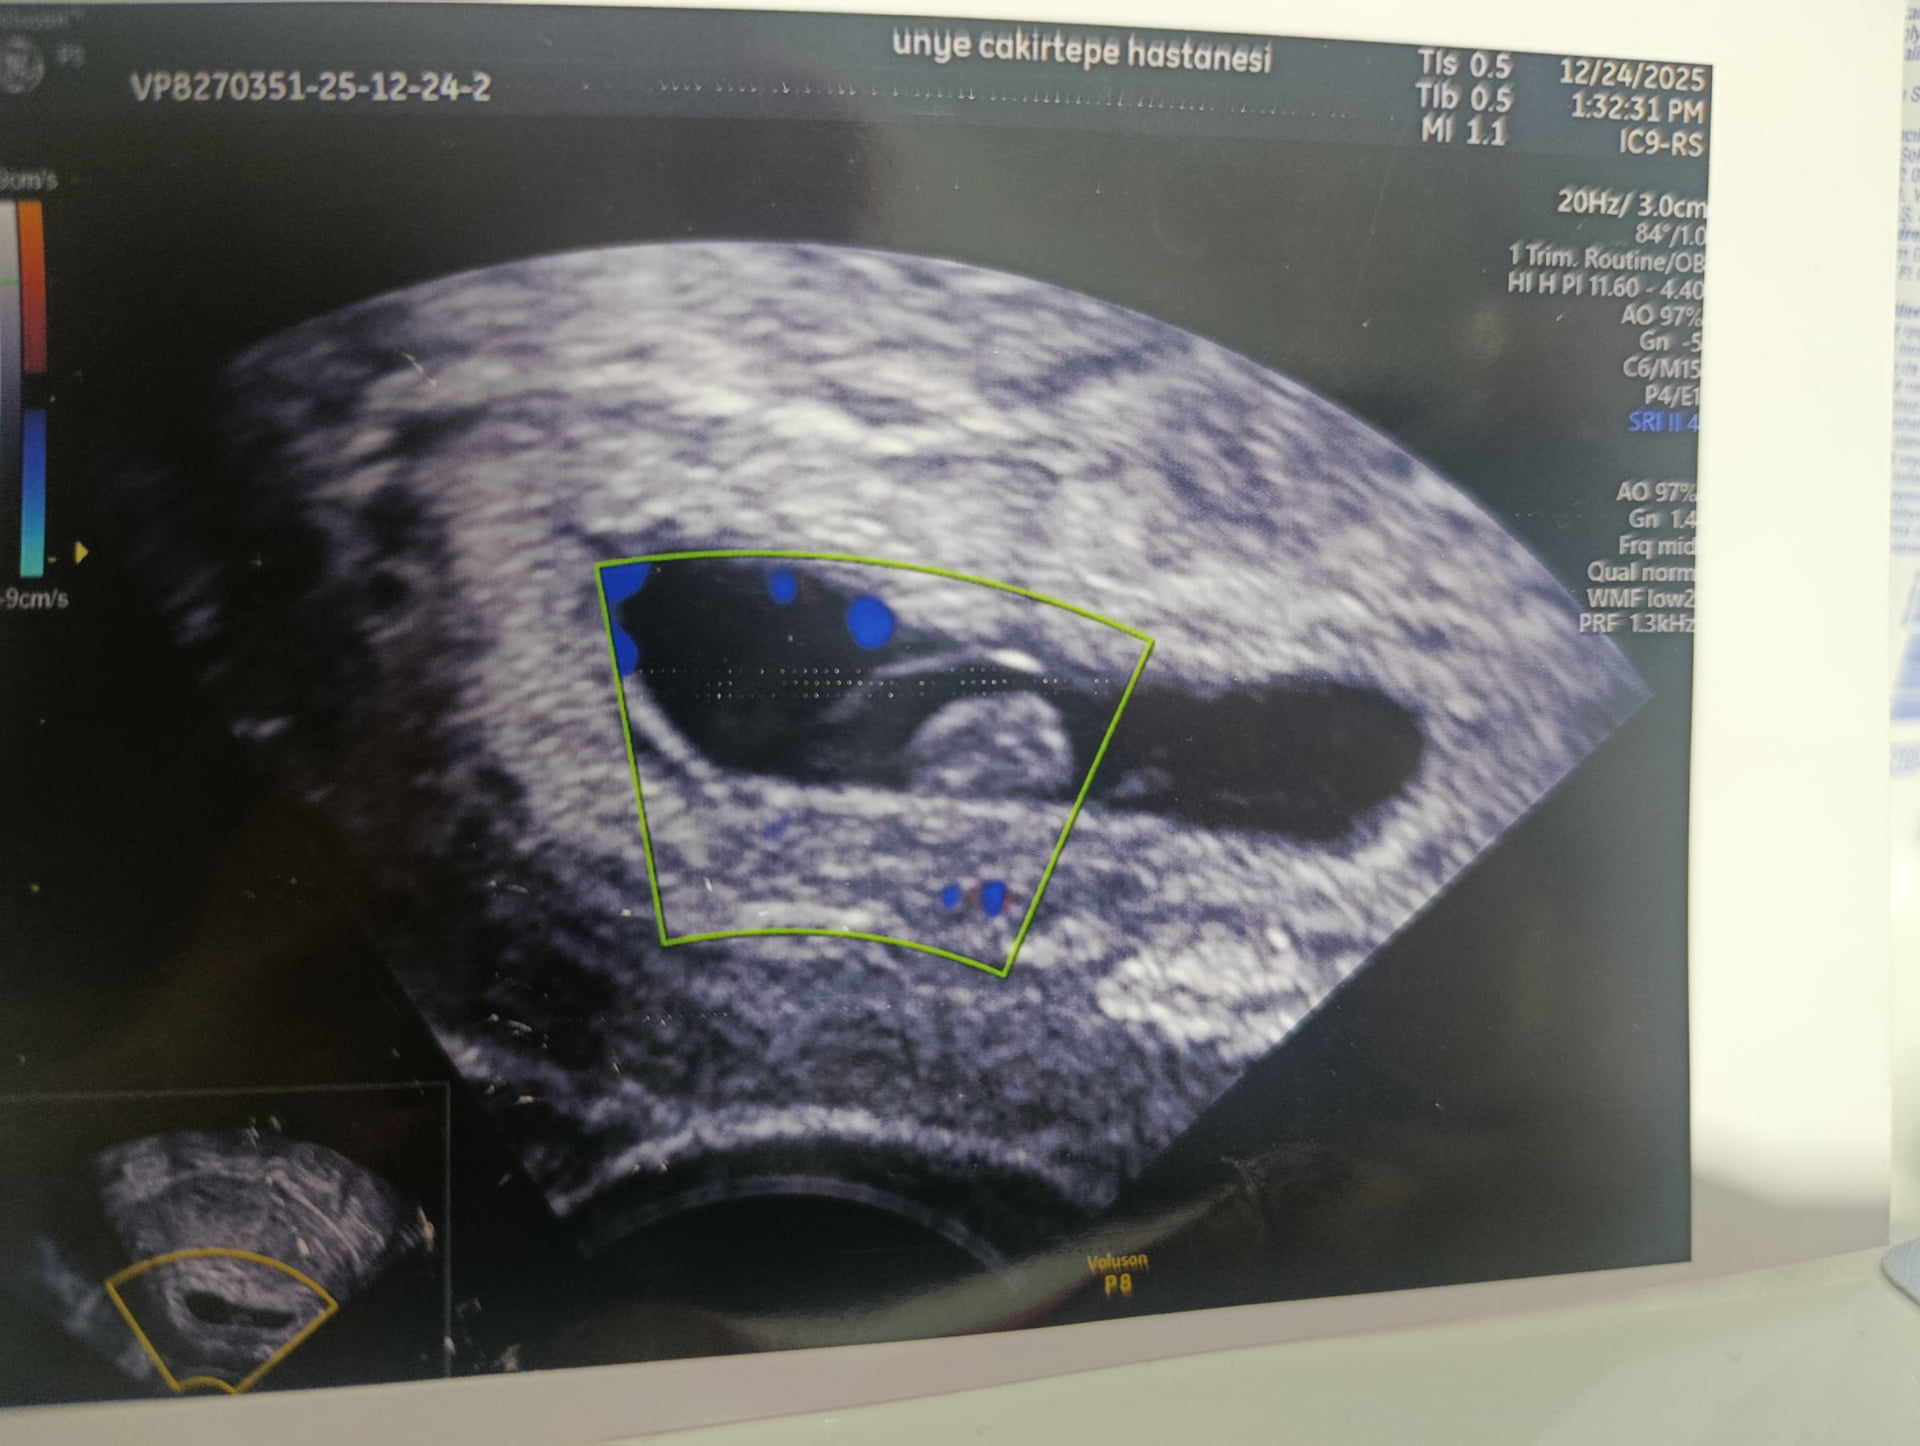

Kızlar 24 Aralık’ta 7+4 haftalıkken bebeğimin kalbi durdu ve 25 Aralık’ta kürtaj oldum ilk gebeliğimdi cinsiyetini çok merak ediyorum acaba bebeğim kız mı erkek miydi keseden cinsiyet tahmini yapar mısınız